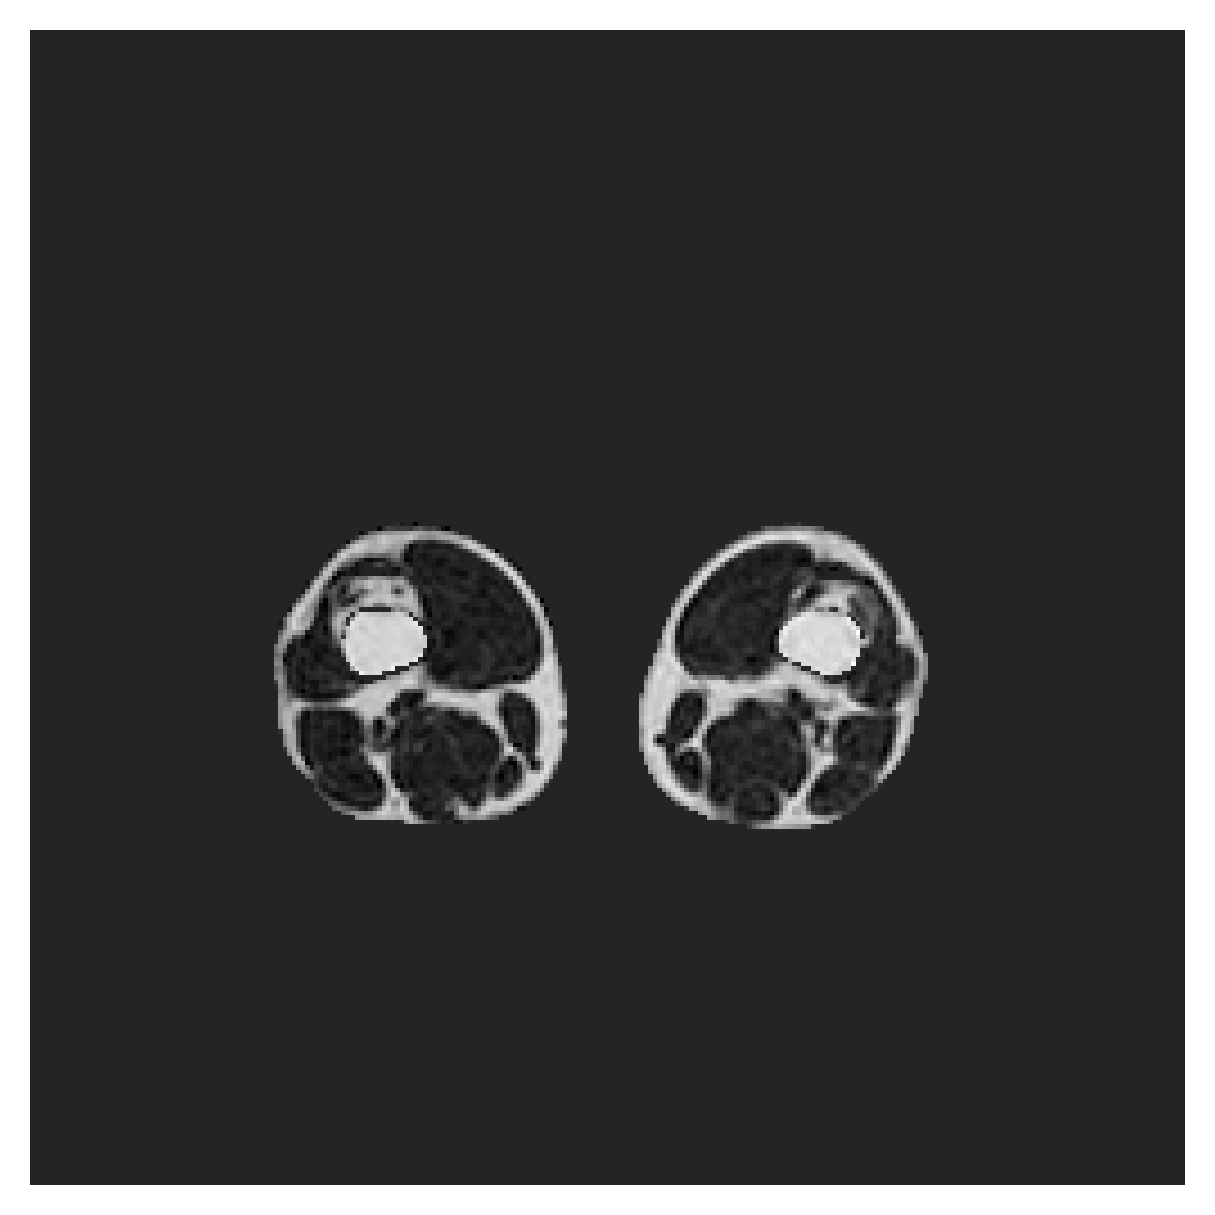

4.4 Evaluation metrics

We evaluate the performance of the methods through two standard segmentation metrics; Dice score (DSC) and 95th percentile Hausdorff distance (HD95). While training is performed on 2D slices, the evaluation metrics are reported on the entire 3D scans.

DSC

The Dice similarity score measures the overlap between the ground truth volume and the output segmentation volume , and is defined as , where denotes the cardinality (in this case the nonzero element count). We report the Dice scores for every foreground organ/tissue, and over all classes.

HD95

The Hausdorff distance is a dissimilarity measure, representing the distance between the surfaces of and . As it is sensitive to outliers, we use the 95th percentile instead of the maximum for computing the directed distances. Again we report the metrics on each foreground class separately, as well as over all classes.